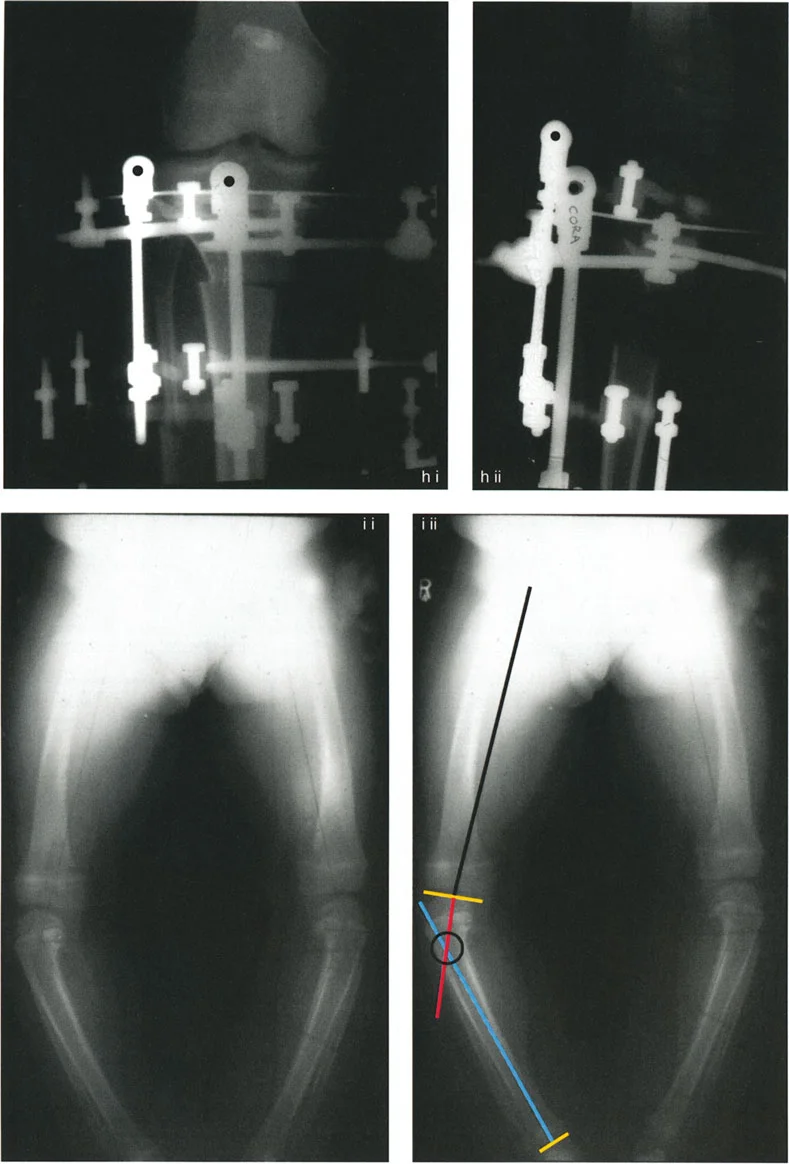

التصوير بالأشعة السينية (X-rays):

- أشعة الساق الكاملة الواقفة (Full-length Standing X-rays): هذه هي الأداة التشخيصية الأكثر أهمية لتشوهات الأطراف. يتم أخذ الصورة بينما يقف المريض، مما يسمح بتقييم المحور الميكانيكي للطرف بأكمله (من الورك إلى الكاحل) تحت تأثير تحمل الوزن. تتيح هذه الصور للجراح قياس زوايا محددة بدقة وتحديد "مركز دوران التشوه" (CORA) – وهو النقطة المحورية التي يجب أن يتم التصحيح حولها.

أهمية التخطيط الدقيق لقطع العظم

إن نجاح جراحة تصحيح تشوهات الأطراف يعتمد بشكل كبير على التخطيط المسبق الدقيق. هذا التخطيط أشبه برسم خارطة طريق هندسية تضمن أن كل خطوة جراحية تقود إلى النتيجة المرجوة. يعتمد هذا التخطيط على "مبادئ بالي" التي تحدد ثلاثة متغيرات هندسية أساسية في كل حالة:

- مركز دوران التشوه (CORA - Center of Rotation of Angulation): هذه هي النقطة المحورية للتشوه في العظم. يحددها الجراح من خلال رسم محاور الطرف قبل الجراحة.

- محور تصحيح الزاوية (ACA - Angulation Correction Axis): هذه هي النقطة التي يدور حولها الجزء البعيد من العظم لتصحيح التشوه. يتحكم الجراح في هذه النقطة عن طريق وضع المفصلات على المثبت الخارجي أو نقطة الارتكاز للوحة التثبيت.

- مستوى قطع العظم (Osteotomy Level): هذا هو الموقع الفعلي الذي يتم فيه قطع العظم. يتحكم الجراح بشكل كامل في هذا المتغير، ويتم اختياره بناءً على عوامل مثل الأنسجة الرخوة، وجودة العظم، ونوع الأجهزة المستخدمة.

النتيجة النهائية للتصحيح تعتمد كليًا على كيفية ارتباط هذه المتغيرات الثلاثة ببعضها البعض. الفشل في التخطيط الدقيق يمكن أن يؤدي إلى "تشوهات ثانوية" غير مرغوب فيها، مثل انحراف المحور الميكانيكي أو ترجمة (إزاحة) العظم.